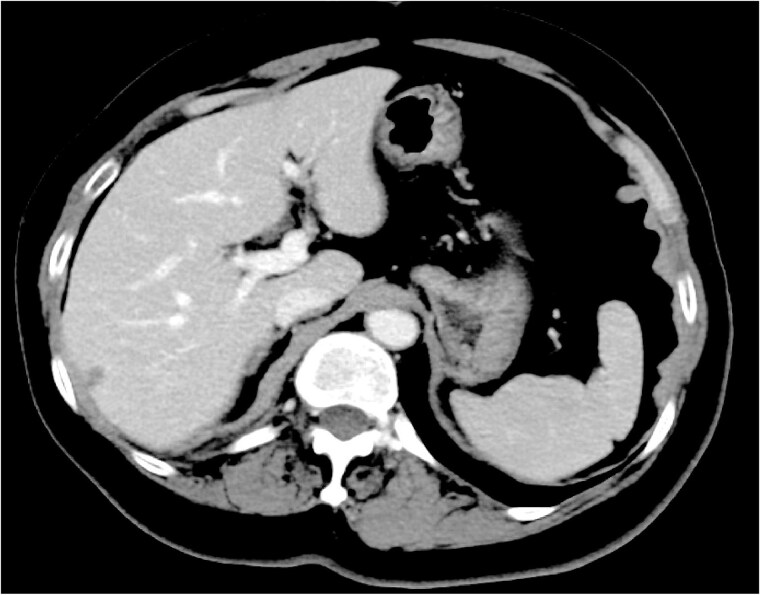

Splenic metastasis is uncommon, and truly isolated splenic metastasis (ISM) from breast cancer is a clinical rarity. Contemporary autopsy series reports splenic involvement in <1% of breast cancer-related deaths, and fewer than 15 well-documented ISM cases have been published. We report a 71-year-old woman presenting with a right-breast mass, regional lymphadenopathy, and a solitary splenic lesion detected on staging computed tomography (CT) and positron emission tomography-CT. Biopsy confirmed hormone receptor-negative, HER2-positive invasive ductal carcinoma. Six cycles of docetaxel, trastuzumab, and pertuzumab led to a 59% reduction in the primary tumour and complete radiological resolution of the splenic lesion. The patient remains progression-free 22 months after initiating therapy, maintained on trastuzumab and pertuzumab. Although extremely rare, ISM can present as the initial manifestation of de novo metastatic breast cancer. Awareness of this possibility may facilitate early systemic therapy and obviate the need for diagnostic splenectomy.